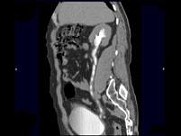

- 多项选择题男,47岁, 腰痛、腰胀2月余伴低热、乏力,结合影像资料所示, 下列哪项说法正确 ( )

A、右侧输尿管多发性狭窄,呈“串珠样”改变

B、右侧输尿管多发性生理性狭窄

C、右侧肾盂轻度积水

D、考虑为右输尿管占位病变

E、考虑为右输尿管结核